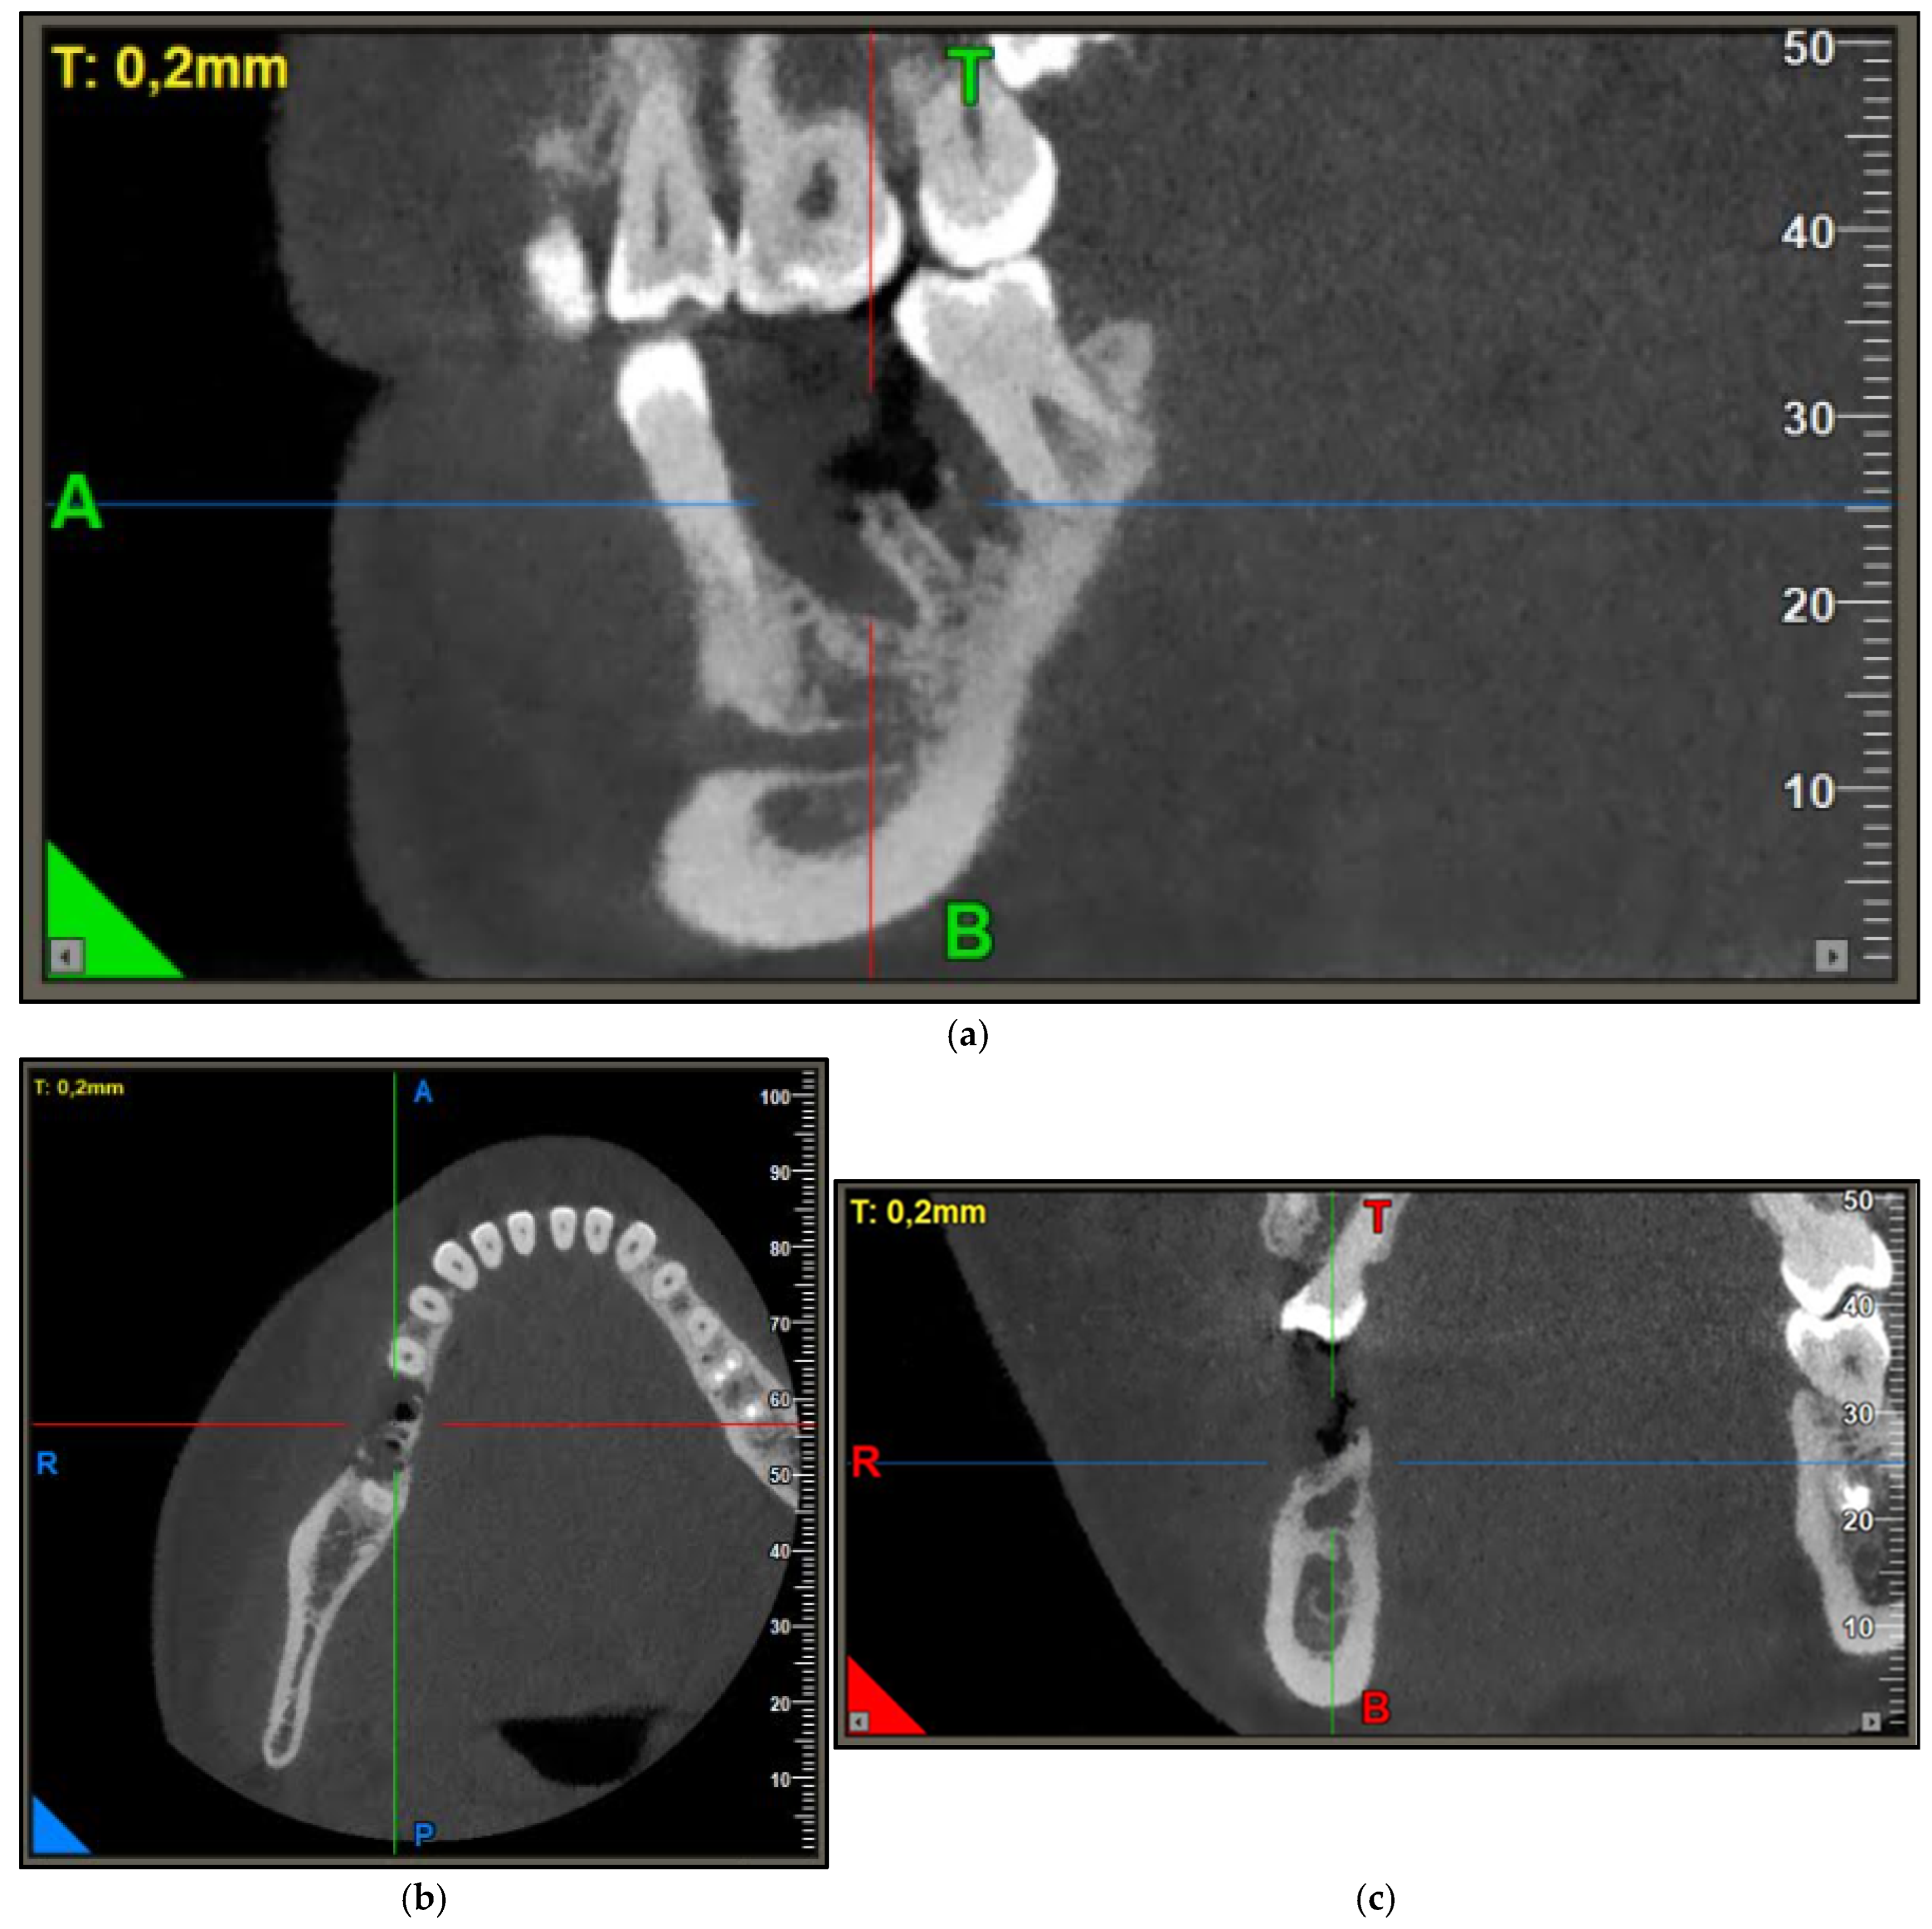

2. Case Report